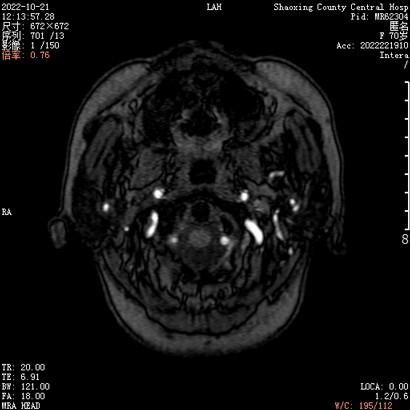

患者入院2月前无明显诱因下出现左侧耳鸣,呈吹风样,持续性,节律与脉搏一致,无明显加重缓解因素,声音与头位或体位无关,无头痛头晕,无恶心呕吐,当时就诊当地医院对症处理,无好转。入院1天前就诊于当地医院查MRA(图1)及脑血管造影(图2)提示“左侧颈外动脉造影见咽升动脉供血通过岩上窦、海绵间窦向双侧颈内动脉引流的动静脉瘘。左侧椎动脉造影显示左侧椎动脉开口无狭窄,椎动脉硬膜支供血向同侧椎旁静脉引流的瘘形成”,现为进一步治疗来院。

根据病史及当地医院辅助检查,诊断后颅窝硬脑膜动静脉瘘明确。分析当地医院MRA及血管造影结果,大致可判断该患者瘘口位于左侧舌下神经管或髁前汇区。详细读片可见左侧颈外动脉造影及椎动脉造影所示引流模式相同。入院后完善脑血管造影检查,并应用双容积影像后处理技术进行三维重建(图3)。便于进一步分析血管构筑,制定手术策略。